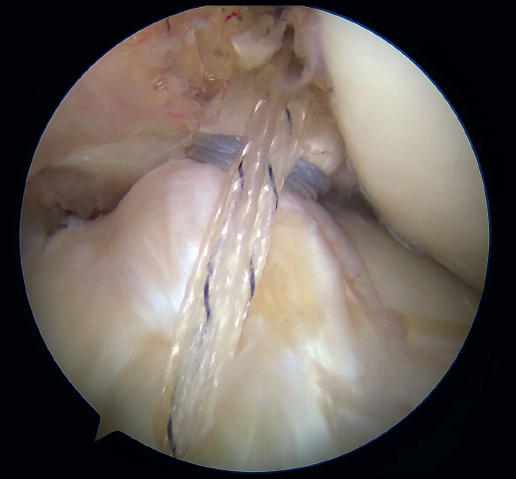

The anteromedial and posterolateral fascicles of the ACL are then identified for suturing separately. Using a suture passer, a closed loop suture is passed through the anteromedial fascicle at its most distal zone, and the loopless extremity is carried alternately (medial to lateral, lateral to medial and so on) to the most proximal zone, usually involving 3 or 4 passes of the suture. The thread may knot on itself during suturing if we are not attentive to it on entry and exit. To solve this problem, we simply undo the knot with retrieval forceps and repeat the step if necessary.

On completion, the thread is retrieved through the accessory anteromedial portal. The process is then repeated, this time with the posterolateral fascicle. To prevent the first thread from breaking with passage of the second thread, it must be ensured that entry and exit in the ligament are very posterior and ideally somewhat proximal to those used for the anteromedial fascicle. Once having reached the most proximal zone after 3 or 4 passes, retrieval is carried out in the same way through the accessory anteromedial portal.

Outside the knee, the threads are loaded into a knotless anchor implant with a tape that will act as anterior reinforcement of the ACL when attached to the tibia. Once the implant has been loaded, it is inserted into the previously prepared site. This step is facilitated when viewing is made from the anteromedial portal, as it affords a better perspective of the zone (Figure 5). Once the implant has been inserted, the suture threads are cut at the level of the condylar wall.